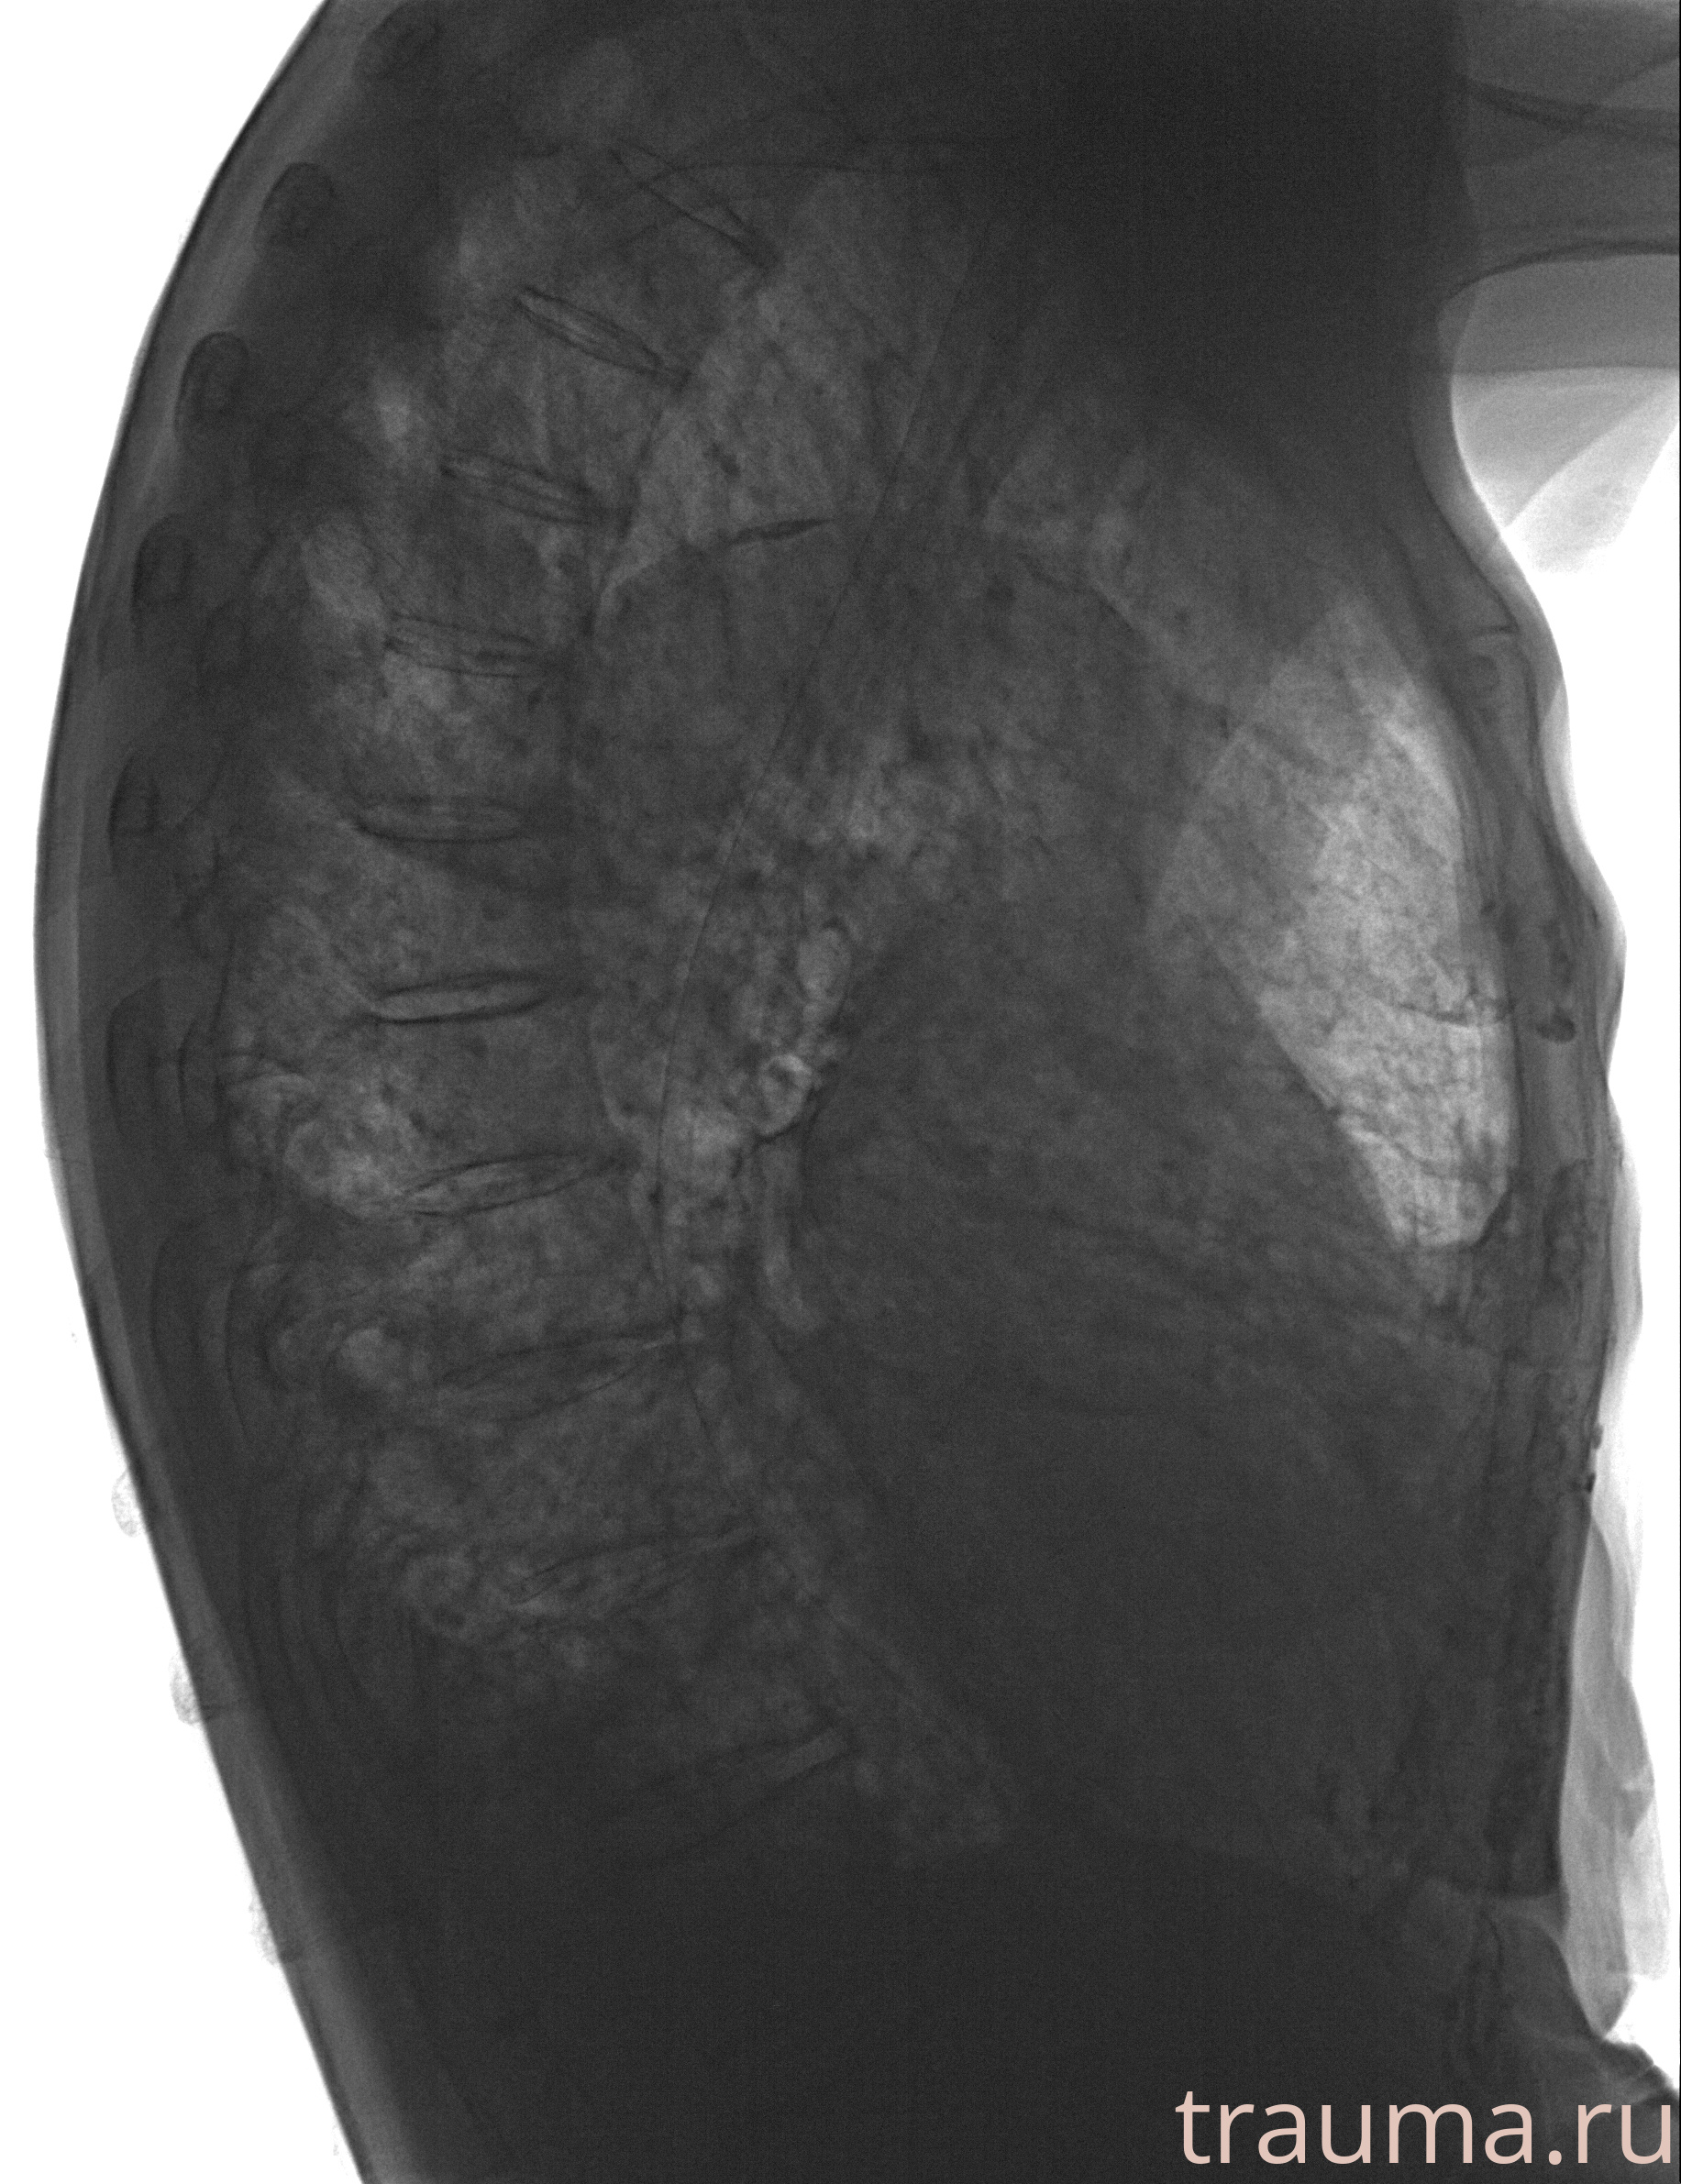

Рентген на дому: по вашему адресу приезжает врач-рентгенолог, травматолог-ортопед с мобильным рентгеновским аппаратом, проводит диагностику травмы или заболевания, делает необходимые рентгенограммы, дает рекомендации по дальнейшему лечению. Получить качественные снимки в домашних условиях возможно благодаря уникальной методике, разработанной МосРентген Центром для института  Склифосовского

при переломе шейки бедра и пневмонии от компании МосРентген Центр - партнера Института имени Склифосовского